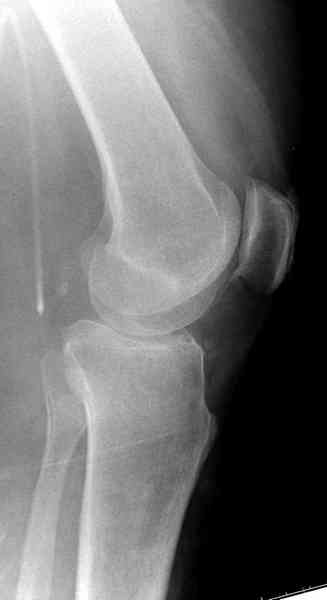

Это техника применяется, когда имеется

центральная импрессия, а при ипрессии с краевым переломом - после приподнимания импрессии опорная (Butress) пластина, как на снимке.